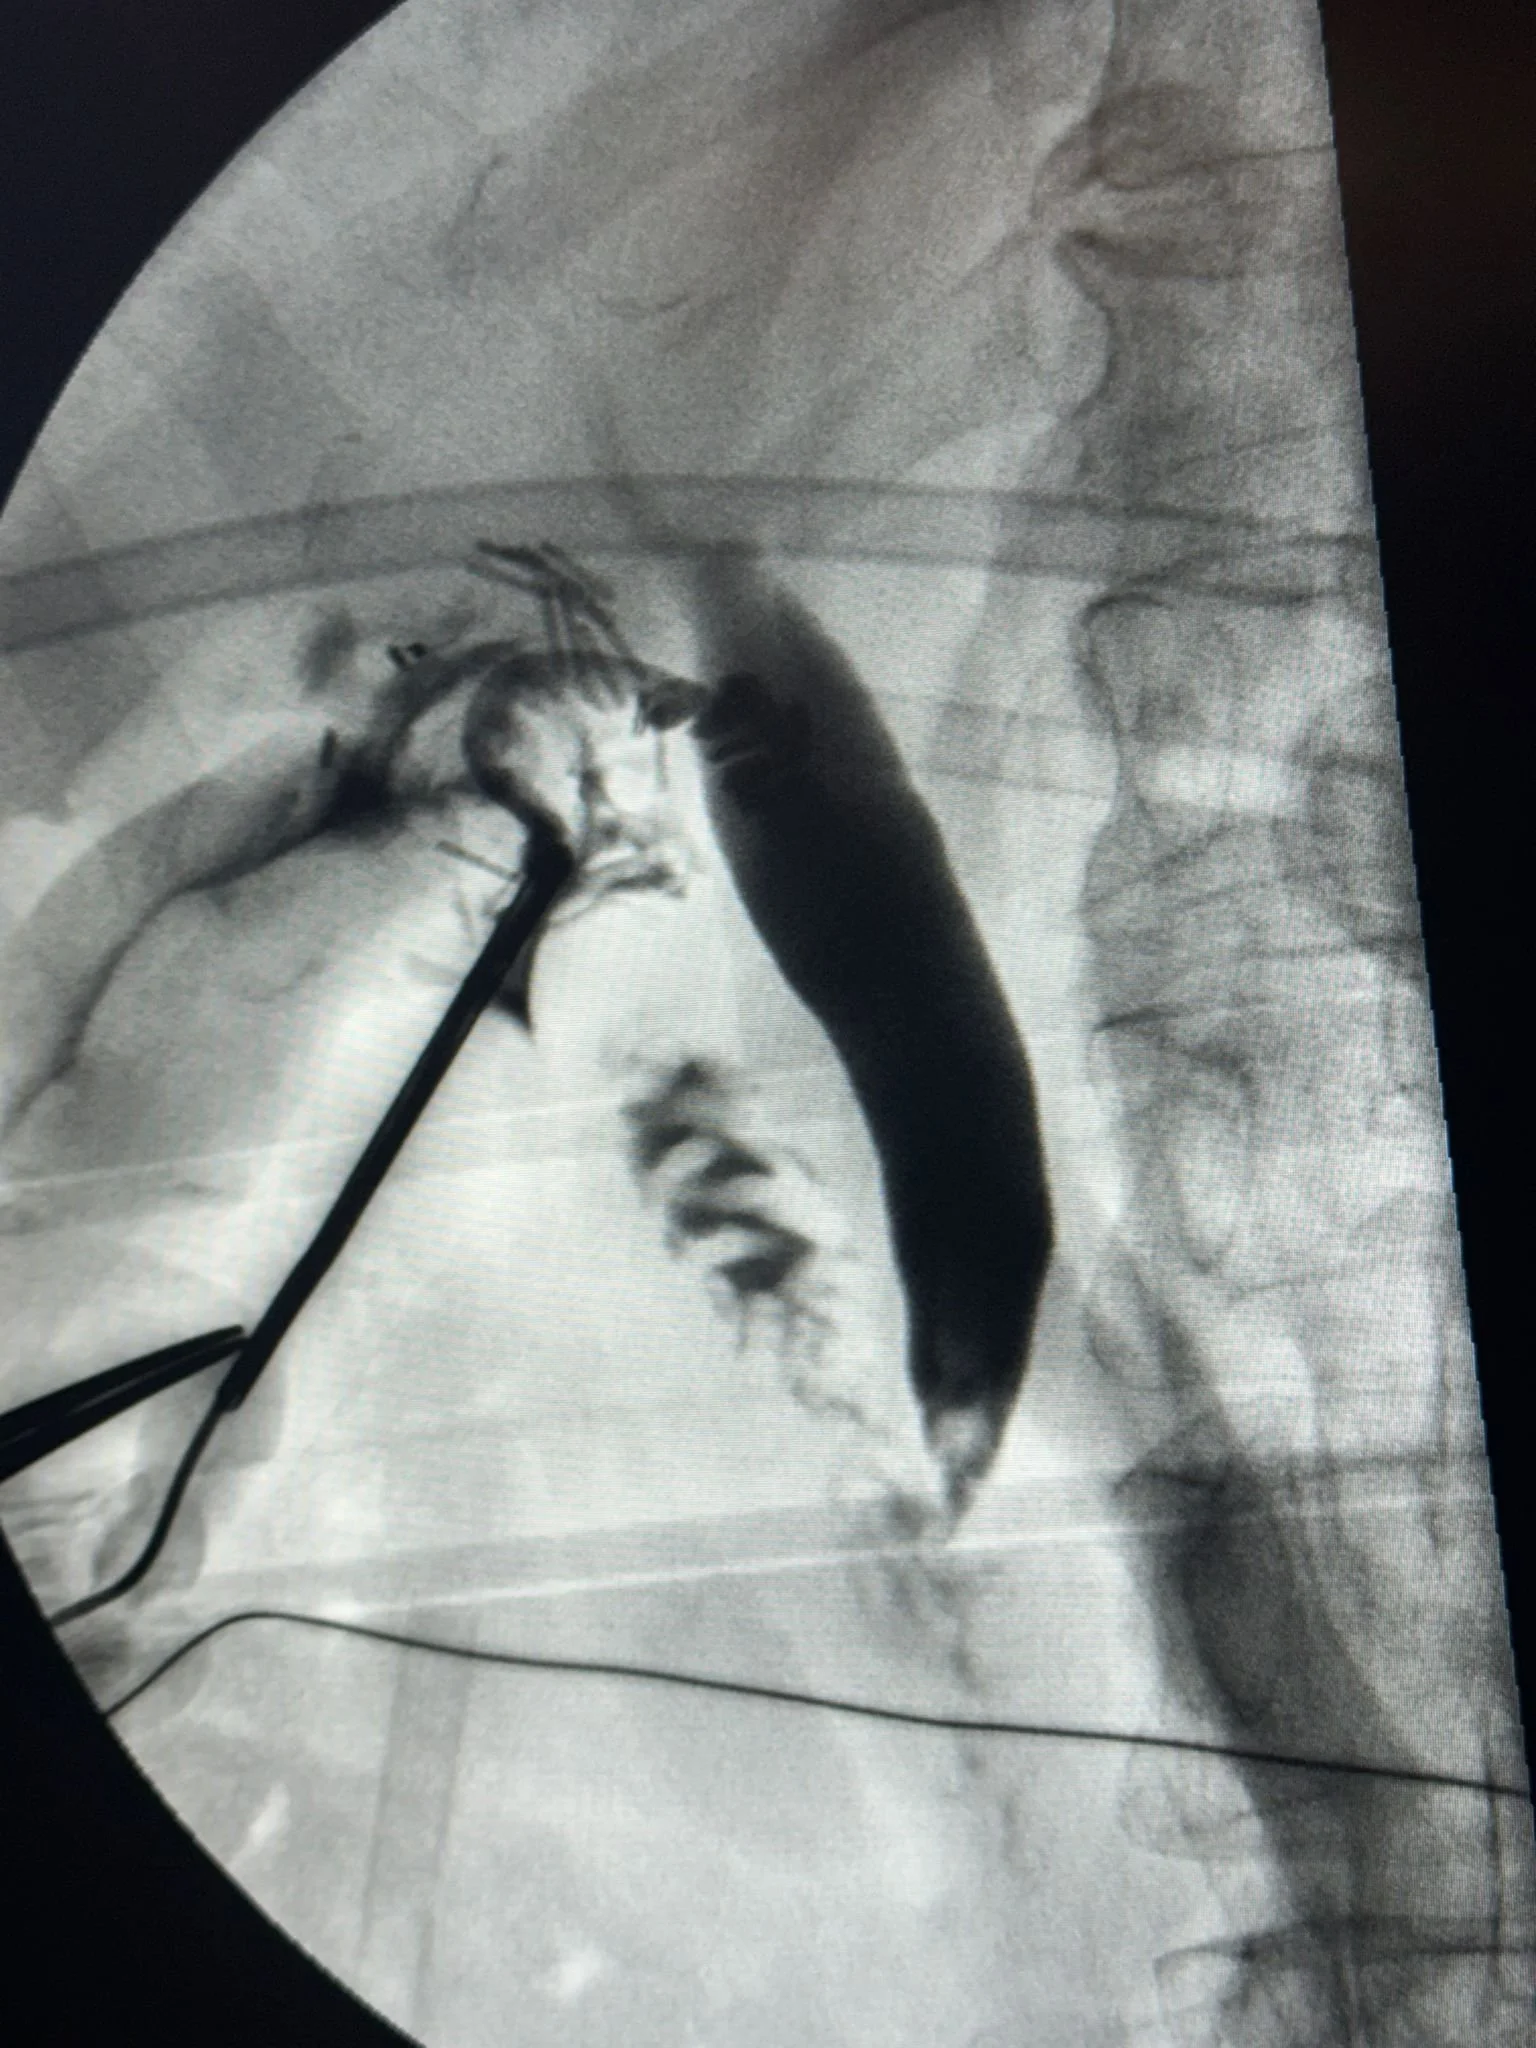

We are also able to image and assess the bile duct during gallbladder removal surgery (known as an intra-operative cholangiogram) to see if any stones have migrated from the gallbladder into the common bile duct (CBD). Common bile duct stones may cause a variety of serious complications such as jaundice, sepsis or pancreatitis.

Common Bile Duct stones

Common Bile Duct (CBD) stones (also known as choledocholithiasis) are stones within the bile duct, which have usually migrated from the gallbladder. Some stones may pass on their own from the bile duct to the intestine, but often these stones will cause further complications such as jaundice, sepsis or pancreatitis and will therefore need to be removed as well as the gallbladder.

At Gallstone Surgery London, our highly specialized surgeon is internationally renowned for the single-stage treatment of common bile duct stones with concurrent gallstones by performing keyhole surgery to extract common bile duct stones at the time of gallbladder removal (Laparoscopic Common Bile Duct Exploration [LCBDE] with cholecystectomy).